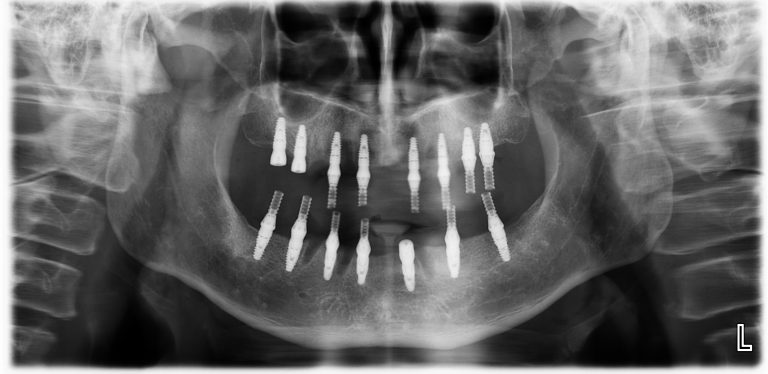

初診時,郭光哲醫師會先了解患者的身體狀況以及有無任何手術禁忌症。確認身體狀況許可後為患者拍攝全口 X 光和電腦斷層影像,接著會了解患者的需求,擬定專屬的治療計畫,並告知詳細的療程費用、保固及注意事項。

植牙手術

手術日早上,郭光哲醫師會依照治療計畫在每顎植入植體,植牙過程在舒眠麻醉下執行,並由專業的麻醉科醫師協助監控,讓患者一覺起來輕鬆完成手術,毫無壓力。

為了追求完美,郭光哲醫師在每個 All on X 手術中都會搭配最新 Navident 4 (AR擴增實境數位導航),完美執行精準與安全。